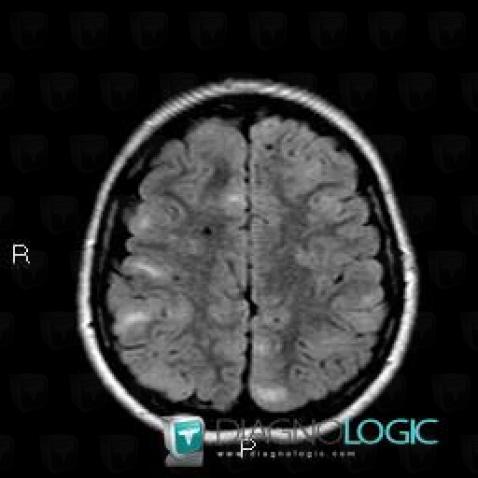

Here is the specific information in the key image above:

- Diagnosis Tuberous sclerosis (link to Hamartoma), Location(s) Cerebral hemispheres, with gamuts Multifocal intracranial lesions, Intracerebral T2W or FLAIR hyperintense lesion

- Diagnosis Hamartoma, Location(s) Cortico subcortical region, with gamuts Subcortical lesion, Cortical lesion

Here is the specific information in the key image above:

- Diagnosis Tuberous sclerosis, Location(s) Cerebral hemispheres, with gamuts Parietal posterior or occipital T2WI or FLAIR hyperintense lesion

- Diagnosis Tuberous sclerosis (link to Hamartoma), Location(s) Cortico subcortical region, with gamuts Cortical lesion, Subcortical lesion